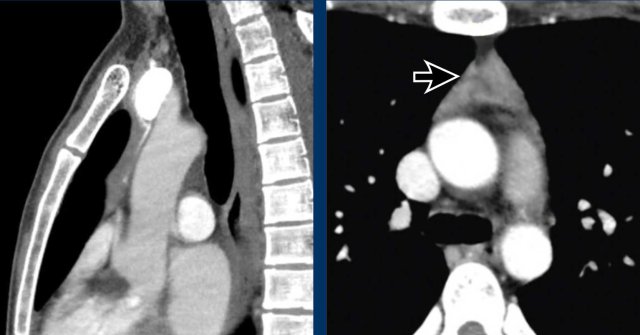

These images are of a 34-year-old female with dyspnoe.

Study the images.

What is your opinion?

Images

There is a cystic mass in the prevascular mediastinal space.

There are thick enhancing walls.

Because it still wasn't clear what we were dealing with a PET was performed.

Continue with the PET images...

Based on the PET-findings which diagnosis is the most likely?

Is it a cystic thymoma, complicated cyst, neuroendocrine tumor or a lymphoma?

The PET shows multiple lesions, which must be pathologic lymph nodes.

Discussion

A thymoma is almost never accompanied by lymphadenopathy.

An infected cyst could also give rise to lymphadenopathy, but not so widespread as in this case.

Final diagnosis

Cystic lymphoma.